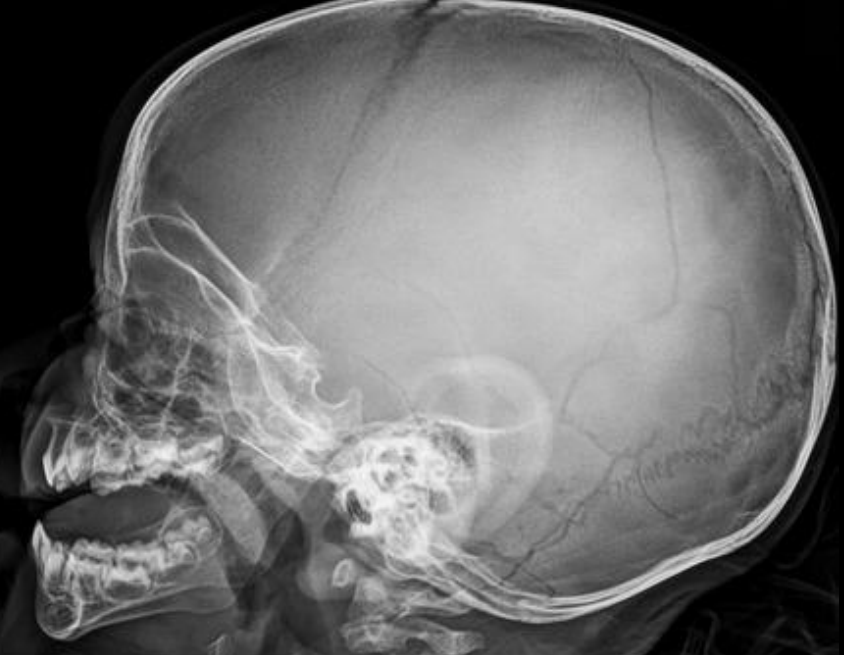

¿Qué diferencia una sutura de una fractura en RX?

• Sutura: borde serrado, línea curva, + clara, 📍 anatómica fija

• Fx: borde liso, línea recta, + oscura, atraviesa suturas

Fractura lineal: hallazgos

Línea radiolucente fina; temporal/parietal + frec